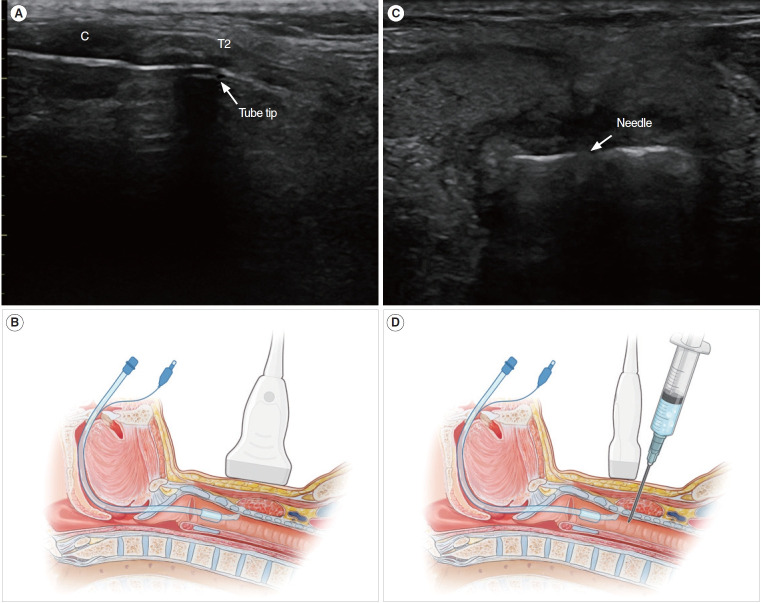

Objectives: Tracheostomy is an important procedure for critically ill patients in the intensive care unit (ICU), and percutaneous dilatational tracheostomy (PDT) has gained popularity due to its safety and effectiveness. However, there are limited data comparing ultrasound-guided PDT (US-PDT) with surgical tracheostomy (ST). In our previous study, we reported that US-PDT had similar safety and effectiveness to ST, with a shorter procedure time. However, the study design was retrospective, and the sample size was small. Therefore, we conducted a randomized controlled trial to demonstrate the safety and efficacy of US-PDT compared to ST.

Methods: A total of 70 patients who underwent either US-PDT (n=35) or ST (n=35) were enrolled in the study between October 20, 2020 and July 26, 2022. The patients were randomly assigned to their respective procedures. The data collected included patient clinical characteristics, procedure time and details, complications, duration of ICU stay, time taken for weaning from mechanical ventilation, and hospital mortality.